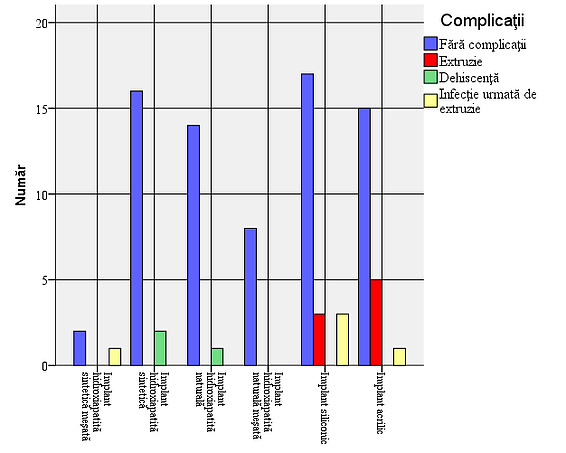

Figure 1: Gender distribution in the study. The presence of a larger number of male patients is due to the large number of eviscerations after ocular trauma, a pathology more frequently encountered in males (33 cases). The implant types were used in a relatively equal proportion: in 26.7% of patients the silicone implant was used, in 25.6% the synthetic hydroxyapatite implant, in 24.4% the acrylic implant, and in 23.3% the natural hydroxyapatite implant.

Figure 2: Types of implants used in the sample In 15 of the patients studied (16.7%), complications were observed: 5 cases of infections, 13 cases with extrusions and 2 cases with dehiscence. Out of the total of 15 cases with complications, extrusion occurred in 86.7%. Considering that all cases of infection were followed by extrusion, the situation of complications that occurred is as follows: 8 cases (8.9% of the total number of patients studied) with extrusion only, 5 cases (5.6%) of infection followed by extrusion and 2 cases (2.2%) with dehiscence. In most of the cases with complications, the association of infection with extrusion occurs, dehiscence not being associated with extrusion or infection.

Figure 3: Frequency of complications – 8 cases (8.9% of the total patients studied) with extrusion only, 5 cases (5.6%) of infection followed by extrusion and 2 cases (2.2%) with dehiscence.

Objective verification: Existence of a link between the type of implant used and the presence of complications

Although it is observed that dehiscence occurred only in cases of hydroxyapatite implants, the very small number of cases prevents us from showing that this type of complication occurs more frequently in the case of these implants.

If we refer only to the individuals in the sample who experienced complications, the results obtained from the application of the chi-square test also show a statistically insignificant difference (χ2=11.750; df=6, p=0.068) between patients with different types of implants in terms of the presence of certain complications, confirming the conclusions shown previously, that is, there is no statistically significant relationship between the type of implant used and the occurrence of a certain type of complication.

From the point of view of biocompatibility, all the tested materials offer the patient a good general rehabilitation, however, the hydroxyapatite implant, whether synthetic or coralline, offers a series of advantages that include a lower incidence of implant extrusion and better resistance to infections. Shields et al demonstrate in 3 consecutive papers on a large number of cases 1 that the presence of conjunctival dehiscence and exposure of the hydroxyapatite implant is reduced. Although acrylic and silicone implants have the added advantage of low cost and immediate availability, there is a higher rate of infection followed by extrusion, observed when considering cases with complications, associated complications requiring surgical reintervention.

- The studied sample includes subjects of both sexes, with males accounting for 55.6%, while females accounting for 44.4%, explained by the high rate of ocular trauma in male patients

- The types of implant were used in a relatively equal proportion: in 26.7% of the patients the silicone implant was used, in 25.6% the synthetic hydroxyapatite implant (FCI3), for 24.4% the acrylic implant (PMMA), and for 23.3% the natural hydroxyapatite implant (Bio-Eye);

- In 15 of the patients studied (16.7%) complications were observed: 5 cases of infections, 13 cases of extrusions and 2 cases of dehiscence. Considering that all cases of infection were followed by extrusion, the situation of complications that occurred is as follows: 8 cases (8.9% of the total number of patients studied) with extrusion only, 5 cases (5.6%) of infection followed by extrusion and 2 cases (2.2%) with dehiscence;

Although it is observed that dehiscence occurred only in the cases of hydroxyapatite implants, the very small number of cases prevents us from concluding that this type of complication occurs more frequently in the case of these implants. This could be explained by the fact that implantation in the scleral sac offers protection from infection and wound dehiscence. On the other hand, there is a greater number of associated complications (infection followed by extrusion) in the case of acrylic and silicone implants, which confer a higher degree of severity to these types of complications, which subsequently require a new surgical intervention to re-prosthetize the anophthalmic cavity. I believe that the choice of the type of implant, although it comes after a process of informing the patient, must also include a cost-effectiveness analysis, weighing up the possibility of new surgical re-interventions, especially in the young population.